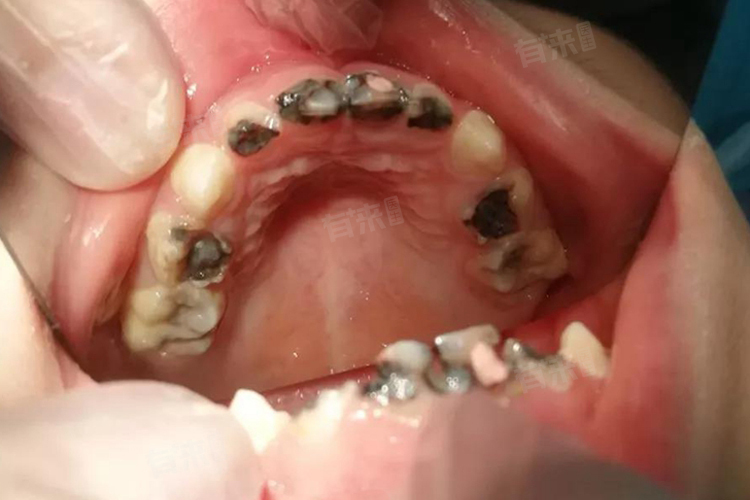

- 另外,当乳牙残根已经严重龋坏,无法进行有效的治疗修复,并且已经没有保留的意义,也应考虑拔除。还有若乳牙残根迟迟不脱落,而对应的恒牙已经开始萌出,形成了“双排牙”现象,这种乳牙残根会阻碍恒牙的正常萌出路径,必须及时拔除,以让恒牙能顺利归位到正常的牙列中。

对于乳牙残根是否拔除,不能一概而论,家长应带孩子到正规的口腔科,让医生通过临床检查、口腔X线片等手段进行综合评估,从而做出最合理的决策。